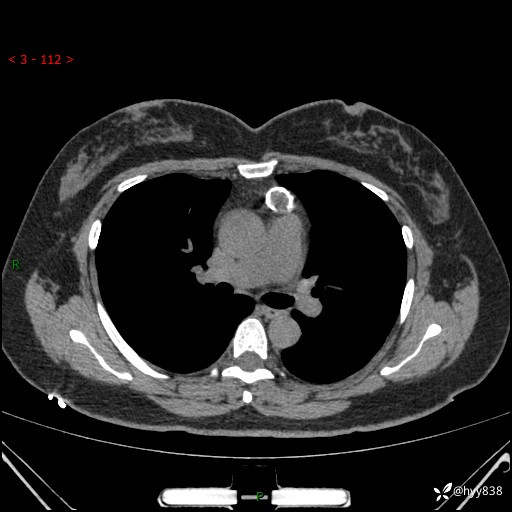

中年女性,检查发现纵隔占位3月余。圆圆的肿物,周围环绕一圈钙化---结果公布~

主诉:检查发现纵隔占位3月余。

现病史:患者于3月前体检行胸部CT检查发现纵隔占位,患者平素无明显咳嗽咳痰,无心慌、胸闷、胸痛、呼吸困难、低热、盗汗,无头痛、头晕,无腹痛、腹胀等不适。现患者欲求进一步治疗,遂来我院就诊,以“纵隔占位”收入我科。 患者自起病以来,精神可,睡眠可,饮食可,大小便正常,体重无明显改变。

胸部CT平扫+增强